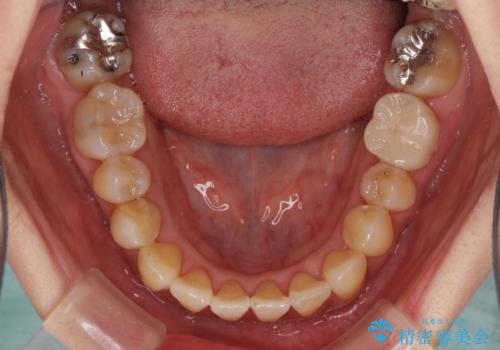

- 前歯の反対咬合により、日々強い痛みを感じているとのことで来院された患者様です。

骨格的に下顎が前方位にありますが、歯列矯正で前歯の被蓋関係を改善することができると判断されたため、インビザラインにより矯正治療を行うこととしました。

前歯が内側に倒れ込む力がかかり、正常な歯ぎしりもできないため、非常に負担のかかりやすい咬み合わせでした。

矯正治療中に上顎前歯が下顎前歯を乗り越える際は、前歯でしか咬めない状況が続くため、食事など不便を感じましたが、治療後には前歯の痛みもなくなり、安定した咬み合わせとなりました。